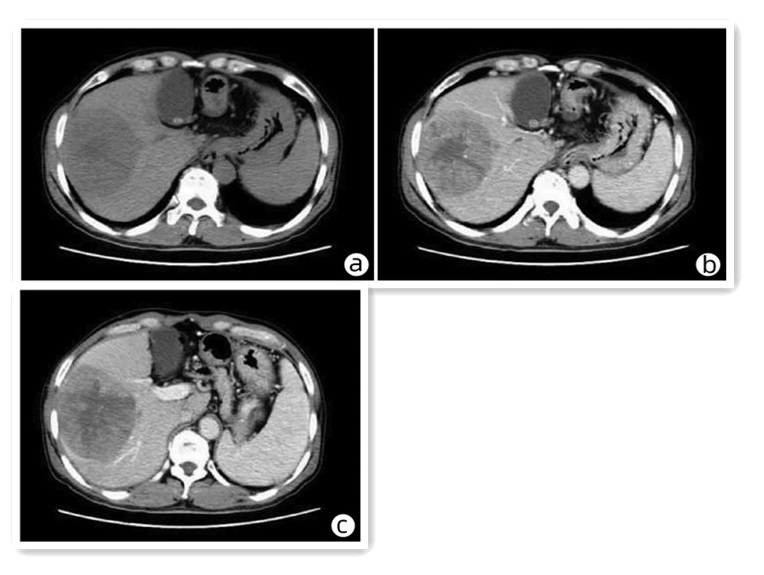

骨髓增生性疾病所致门静脉海绵样变性1例报告

韩冰, 涂传涛

2023, 39(6): 1414-1417. DOI: 10.3969/j.issn.1001-5256.2023.06.025

摘要(798) HTML (257) PDF (2374KB)(45)

摘要: